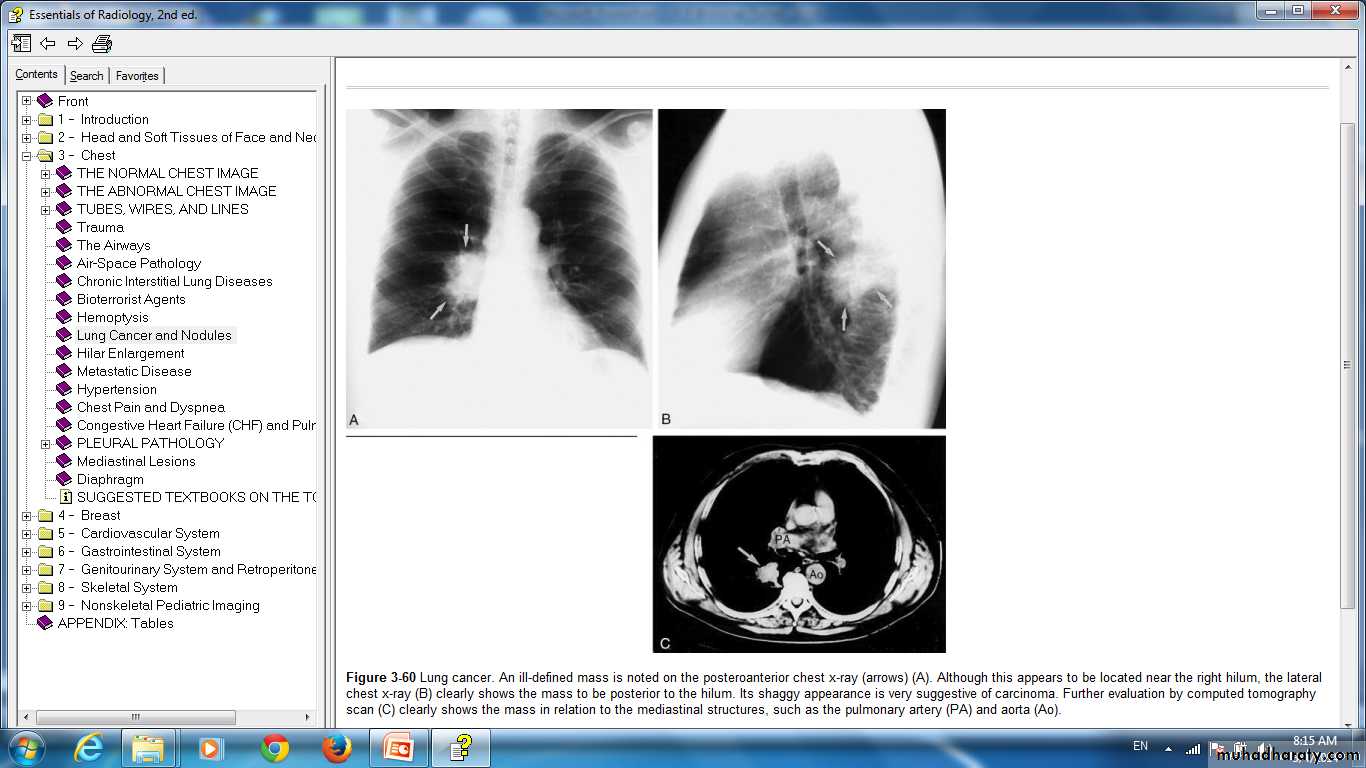

Lung cancer. An ill-defined mass is noted on the posteroanterior chest x-ray (arrows) (A). Although this appears to be located near the right hilum, the lateral chest x-ray (B) clearly shows the mass to be posterior to the hilum. Its shaggy appearance is very suggestive of carcinoma. Further evaluation by computed tomography scan (C) clearly shows the mass in relation to the mediastinal structures, such as the pulmonary artery (PA) and aorta (Ao).